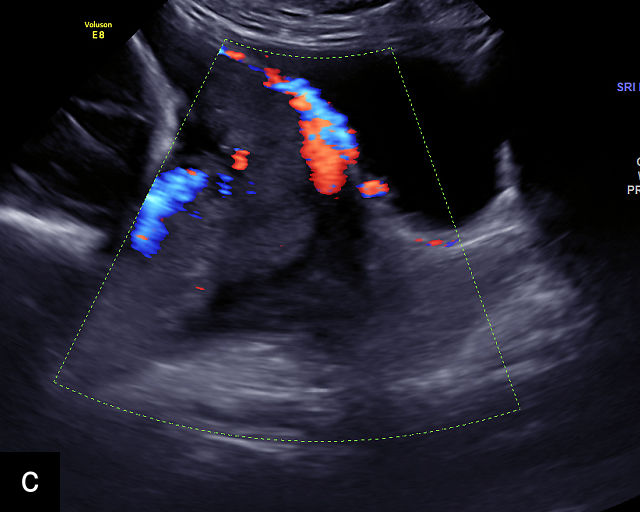

6

Placenta accreta spectrum. (a,b) Sagittal transabdominal grayscale ultrasound of the lower uterus and cervix demonstrating placenta previa accreta, with the placenta (p) containing prominent irregular hypoechoic lacunae. There is absence of the myometrium at the bladder (b) interface (arrows) c, cervix. (c) Sagittal transabdominal color Doppler ultrasound of the lower uterus and cervix demonstrating placenta previa accreta, with increased vascularity of the lower uterus and the myometrial bladder interface. (d) Transvaginal ultrasound of placenta previa accreta showing multiple lacunae involving the cervix with no clear demarcation between the placenta and the cervix. (e) Transvaginal ultrasound of placenta previa accreta showing multiple large irregular lacunae involving the cervix with no clear demarcation between the placenta (p) and the cervix. The placenta has a ‘moth-eaten’ appearance. There is loss of myometrium (arrows). (f) Transvaginal ultrasound of placenta previa accreta without and with color flow Doppler showing multiple large irregular lacunae. The placenta has a ‘moth-eaten’ appearance. There is hypervascularity of the myometrial interface. (g) Transvaginal ultrasound of placenta previa accreta showing multiple lacunae involving the cervix with no clear demarcation between the placenta and the cervix. (h) Transvaginal ultrasound of placenta previa accreta with color flow Doppler showing hypervascularity of the myometrial interface and irregularity of the bladder wall. b, bladder; p, placenta. (i) Transabdominal grayscale ultrasound of cesarean scar pregnancy. The uterine fundus (f) is empty (arrowhead). The gestational sac (arrow) is located in the lower uterus, anterior to the uterine canal, and lies above the cervix (c). b, bladder. (j) Transvaginal grayscale ultrasound image of cesarean scar pregnancy showing the empty fundus (f) and the normal cervix (c). The gestational sac lies below the fundus, above the cervix and anterior to the uterine cavity. (k) Transvaginal grayscale ultrasound image of cesarean scar pregnancy showing the empty cavity (arrowheads) of the uterine fundus (f), and the normal cervix (c). The gestational sac lies below the fundus, above the cervix and anterior to the uterine cavity (arrow).

Several characteristic sonographic findings are associated with PAS.90,95,96,97 These include placental lacunae, which appear as hypoechoic, irregular spaces within the placenta with high-velocity turbulent flow on color Doppler.16,50 Other features include obliteration of the retroplacental clear space, thinning of the myometrium in the lower uterine segment, irregularity and hypervascularity of the myometrial–bladder interface, and placental bulging into the bladder (Figure 6a–h).90,96,98,99